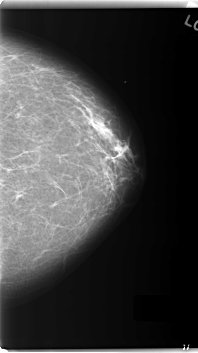

C_0163_1.RIGHT_MLO

C_0163_1.LEFT_MLO

LEFT_MLO LINES 5968 PIXELS_PER_LINE 3464 BITS_PER_PIXEL 12 RESOLUTION 50 OVERLAY

FILE: C_0163_1.LEFT_MLO.OVERLAY

TOTAL_ABNORMALITIES 1

ABNORMALITY 1

LESION_TYPE MASS SHAPE OVAL MARGINS MICROLOBULATED

ASSESSMENT 5

SUBTLETY 5

PATHOLOGY MALIGNANT

TOTAL_OUTLINES 1